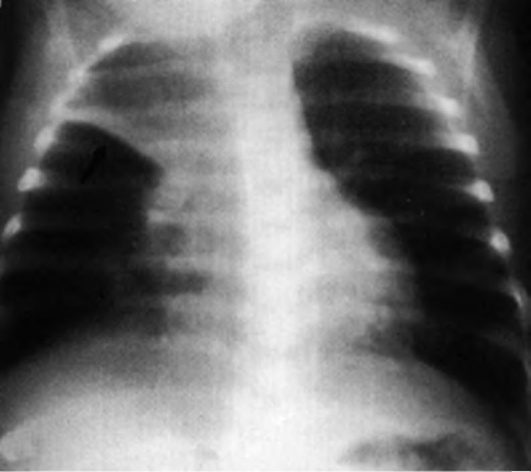

Дополнительный метод диагностики - рентгенография шейного отдела в переднезадней и латеральной проекциях (рис. 3-2). Проведение исследования - иногда причина отсрочки восстановления проходимости дыхательных путей. Рентгенографию необходимо выполнять только при сомнительном диагнозе и при сопровождении ребенка врачом, владеющим методикой интубации. Рентгенографию производят в вертикальном положении ребенка. Не следует пытаться получить рентгенограммы у больных с тяжелыми расстройствами дыхания. Диагностические признаки - тень надгортанника при увеличенном объеме набухшей мягкой ткани и, что более важно, округленный и утолщенный край черпалонадгортанных складок (положительный «симптом большого пальца»). Однако отрицательные данные рентгенографии не исключают эпиглоттит, особенно в ранней стадии. Для диагностики рекомендуют использовать ультразвуковое исследование (УЗИ).

Рис. 3-2. Рентгенологическая картина при эпиглоттите: а - норма; б - симптом большого пальца